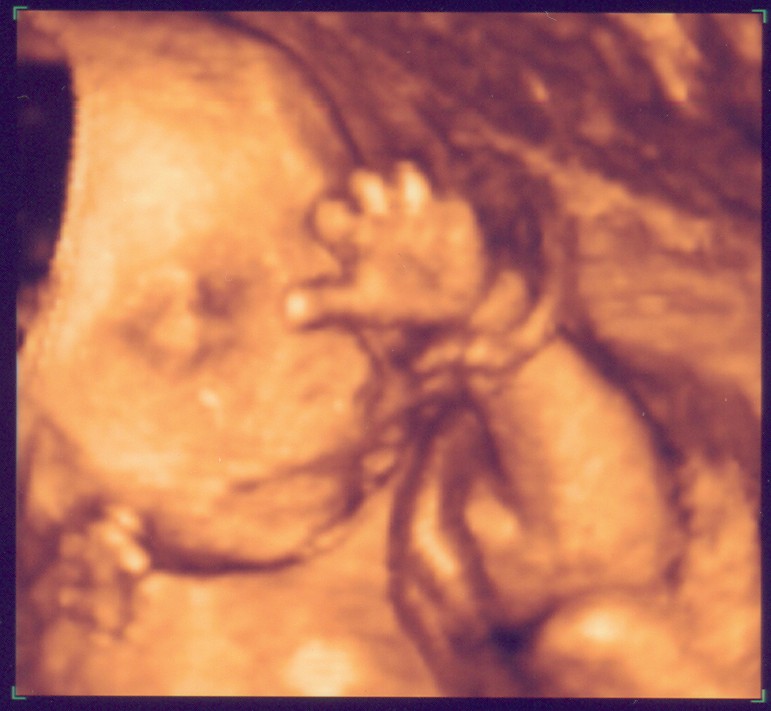

Rechtes Kind im 3D-US

Eure Bilder sind echt toll. Wenn ich mich jetzt nicht allzu blöd anstelle, seht Ihr gleich das aktuellste von unserem Baby. Mit 3-D kann man schon sehr schön alles erkennen, aber wir haben auch ganz schaurige Bildchen. Kommt immer darauf an, wie die Mäuse posieren. :wink: